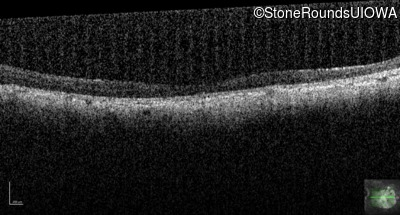

Optical Coherence Tomography - Left - 10/200 sc

Exemplar / OCT Stack

OCT Stack